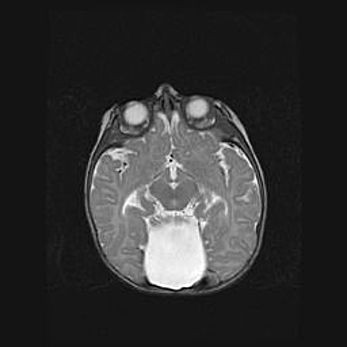

Подострая гематома правой гемисферы мозжечка.

Наружная гидроцефалия.

Возраст: 15 дней

Вес: 3100 г

Пол: женский

Окружность головы: 37 см

Срок гестации: 35-36 недель

При открытой наружной форме гидроцефалии у новорожденных расширяются и переполняются субарахноидные пространства.

Кровоизлияния в мозжечок имеют две клинико-анатомические формы: полушарные гематомы и кровоизлияния в червь.

К появлению этой патологии может привести: повреждения головного мозга, возникающие в результате асфиксии и гипоксии плода при беременности, или травмы во время родов. Редко гематома мозжечка может быть результатом первичной коагулопатии и сосудистой мальформации, диссеминированном внутрисосудистом свертывании, изоиммунной тромбоцитопении.